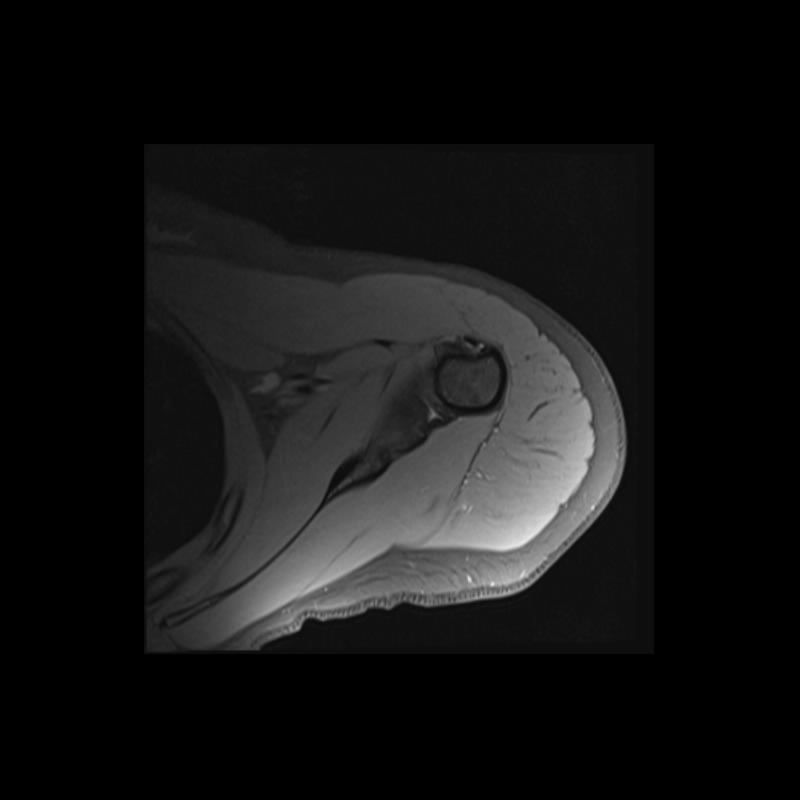

Shoulder MRI Anatomy